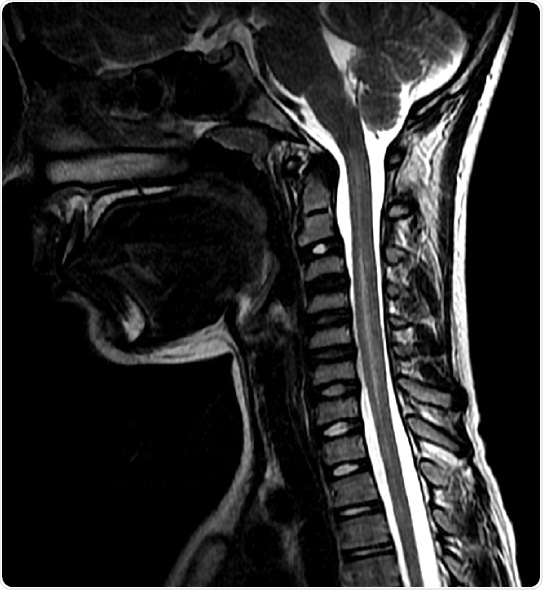

The Centers for Disease Prevention and Control (CDC) defines AFM as weakness in one or more arms or legs as well as damage to the gray matter of the spinal cord as detected by magnetic resonance imaging (MRI). But, the researchers thought that other illnesses that affect the spinal cord and nervous system were getting lumped in with the AFM cases

Those patients with definitive AFM had a fever or viral infection before the onset of weakness in the arms or legs. They also lost function of their limbs in one side of the body first with the majority of children losing function of a single limb or all four eventually. The children with definitive AFM also had many white blood cells in their spinal cords, and less protein in their cerebral spinal fluid than the children with alternative diagnoses. And the children with AFM had only had damage in the spinal cord’s gray matter ¾ where the bodies of the nerve cells reside ¾ and not in the white matter—where the connections between nerve cells that send messages back and forth reside—or the brain like those cases with alternative diagnoses. Children with AFM respond better with infusions of immunoglobins—a collect of antibodies that can help tag pathogens as invaders so the immune system can eliminate them.